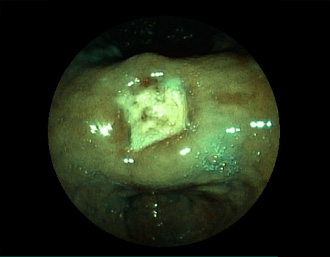

症例2:胃がん(66才男性)

術後胃(B-Ⅱope magen:十二指腸潰瘍手術)。吻合部の後壁側、軽度陥凹の白色病変を認める。生検:Group 5、Signent-ring cell carcinoma(印環細胞癌)と診断[早期胃癌]。高次医療機関へ紹介となり、残胃全摘術(リンパ節郭清)を行いました。